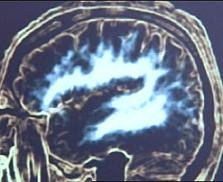

Un estudio que se ha realizado en Barcelona por investigadores catalanes, ha mostrado por primera vez en imágenes qué ocurre en el cerebro de un bebé cuando adquiere el vocabulario entre los 18 y 24 meses de edad. Las áreas del cerebro relacionadas con el lenguaje maduran y la mielina cubre estas áreas (zona blanca en la foto), entonces, automáticamente el niño pasa de realizar balbuceos a poder hablar.

Este descubrimiento posibilitará, según el neurólogo Jesús Pujol, ayudar a los niños que tengan problemas con el lenguaje, ya que gracias a estas imágenes se puede estudiar el tiempo en el que ocurren los cambios y hacer un seguimiento para determinar las causas del problema.